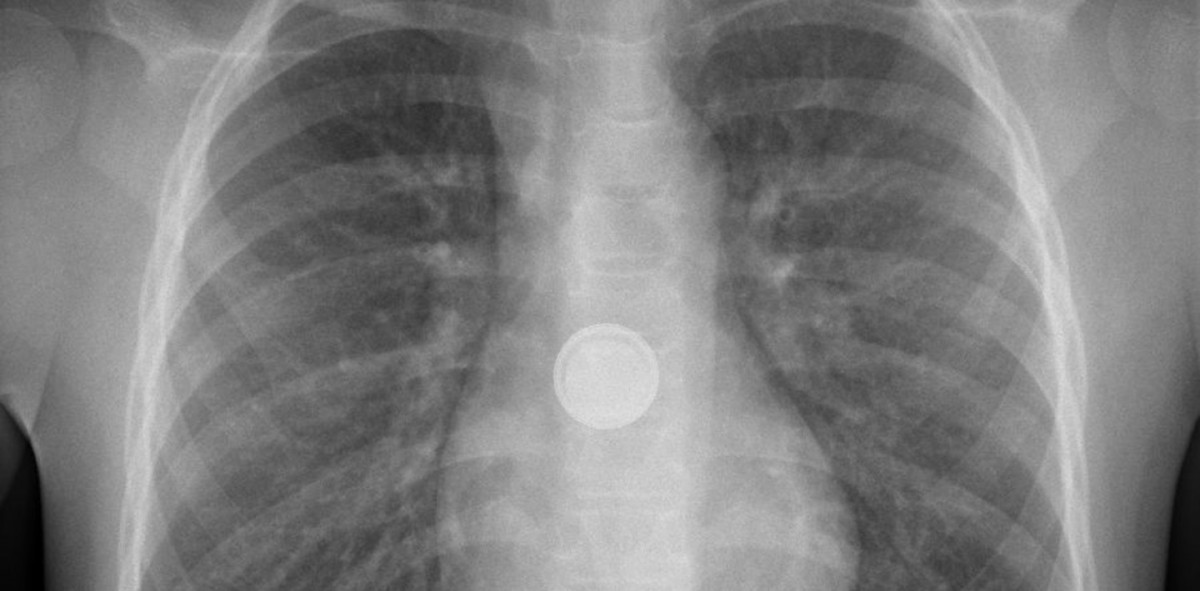

Bei der nationalen Notrufstelle Tox Info Suisse gehen pro Jahr im Schnitt rund 60 Anfragen in Zusammenhang mit Knopfbatterien ein. Rund zwei Drittel davon betreffen Kinder unter sechs Jahren. Verschluckt ein Kind eine solche Batterie, kann das in selten Fällen zu Verätzungen der Speiseröhre führen. Dies geht aus dem Bericht «Massnahmen gegen die Gefährdung der Gesundheit von Kindern durch Knopfbatterien» zur Erfüllung des Postulats 21.3788 hervor. Im Vergleich zu den gesamten Unfällen in der Schweiz, sind Knopfbatterien kein Unfallschwerpunkt. Die Beratungsstelle für Unfallverhütung behandelt das Thema im Rahmen der generellen Prävention von Verschluck-Unfällen regelmässig in ihren Informationen und macht darauf aufmerksam, dass solche Batterien konsequent ausserhalb der Reichweite von Kindern aufbewahrt werden müssen. Zudem gelten für Spielzeuge mit Batterien spezielle Anforderungen zur Sicherung von Batteriefächern.